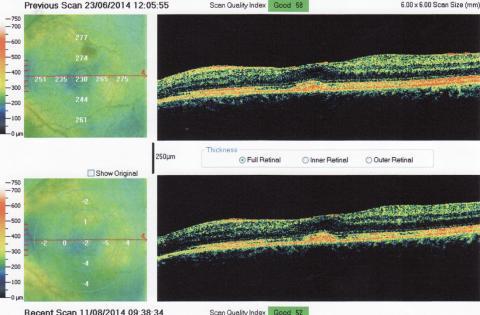

Pro větší náhled klikněte na obrázek

Dobrý den, aktuálně beru léky (dlouhodobě) Medrol 4mg a Sandimun 150mg, pro léčení nespecifikoveného autoimunitnho onemocnění které mi opakovaně "napadá" sítnici záněty. Aktuálně mě nejvíc trápí levé oko (viz snímek z OCT) 1) Od snížení Medrolu pod 16mg (cca před 4 měsíci) mě trápí nějaké nervové dráždění levého oka, které jak sem vypozoroval bylo "vyprovokované" při obou návštěvách na očním kdy mi rozkapávali oči a dívali se na sítnici. Než sem mi to po předminulé návštěvě uklidnilo trvalo to skoro měsíc ale měl sem klid až do další oční kontroly kdy to začalo znova. Můj oční doktor mi řekl že to může být způsoběno tím jak se oční specialista dívá na sítnici krom toho přístroje ještě čočkou kterou přikládá těsně před oko a to co mě dráždí je rohovka. Mě to ale připadá že mě to dráždí až někdě vzadu jak je sítnice nebo jěště dál když s okem nehýbu tak je to celkem v klidu a jek jím pohnu tak to je jako by mi někdo přejel přes nervy, a když je to opradvu hodně silné tak mi při tomto cuká celé oko a trá mi to s obrazem na který se dívám, ale když se dívám do zrcadla tak zornička se nechýbe, jednou to došlo tak daleko že mě to "vytřelovalo" až do uší a měl sem s toho závratě. Byl sem i na MR a nemám RS 2) Je možné odstranit nebo snížit jejich vnímání i jinou metodou než vitrektomii kterou bych mohl podstopouti i když trpím na chronické záněty sítnice 3) Když mám po poslední velké atatce (v 10/2013) v zorném nějaká slepá místa, je možné s tím něco dělat nebo zlepšít vidění nějakou operací ?